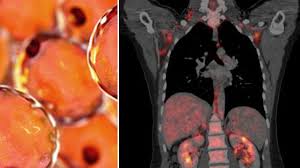

Scienza e indagini moderne

Oggi, le tecnologie avanzate offrono nuove possibilità.

Analisi del DNA e studi antropologici potrebbero fornire risposte più precise, ma il percorso è complesso e non privo di ostacoli. La conservazione dei resti rappresenta una sfida.

Gli esperti lavorano per ricostruire la verità.